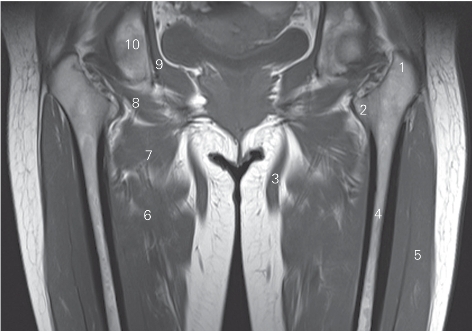

图5-16 经股骨长轴的冠状断层MR T1加权图像

1 大转子 greater trochanter 2 小转子 lesser trochanter

3 股薄肌 gracilis 4 股骨 femur

5 股外侧肌 vastus lateralis 6 大收肌 adductor magnus

7 短收肌 adductor brevis 8 闭孔外肌 obturator externus

9 闭孔内肌 obturator internus 10 坐骨 ischium